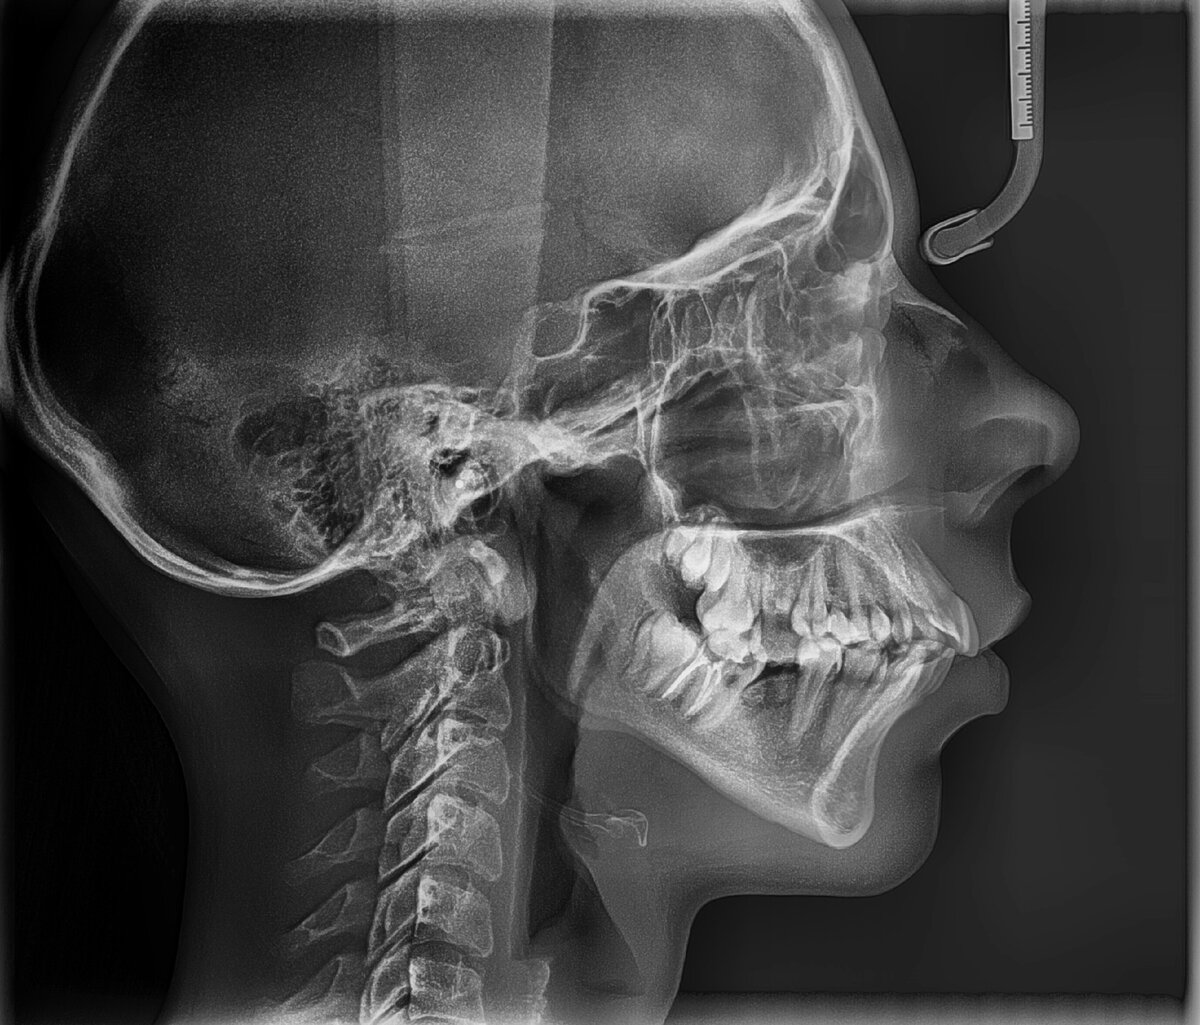

ТРГ

• Телерентгенограмма (ТРГ). Рентгеновский снимок головы, который используется в ортодонтии. Помогает оценить состояние прикуса и спланировать его коррекцию. Позволяет увидеть угол наклона челюстей, их соотношение, размер и так далее.